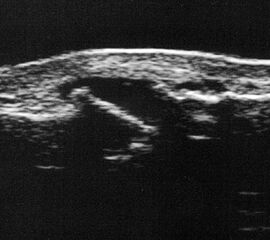

Abgehobenes Periost mit periostalem Hämatom (rechts) mit Gegenseite (links). Die Kortikalis wird unterbrochen von der noch offenen Wachstumsfuge der Fibula.

Abbildung 12

Lagerung: Rückenlage, leichte Innrotation des Fußes.

Schnittebene: LS über distaler Fibula.

Referenzstruktur: Fibula im Längsverlauf.

Befunde: Bei Kindern wird nach Distorsion des OSG mitunter eine Lösung der Fibulafuge vermutet, die jedoch in der klinischen Praxis sehr selten ist. Die seitenvergleichende Untersuchung zeigt dann ein aufgrund des dicken und bei Kindern gut abgrenzbaren echogenen Periosts ein periostales Hämatom, was aber auch ein Hinweis auf eine Fissur oder Fraktur sein kann (Abb.12).